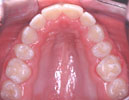

Patient Example

Treatment Time: 7 months and 1 week

This

11 year old female presented with a Class II moderately crowded malocclusion

with 8-10 mm of excess overjet. The parents chose the Accelerated

Osteogenic OrthodonticsTM procedure in preference

to conventional braces/extractions/retraction or conventional braces/orthognathic

surgery. The upper first bicuspids were removed prior to beginning

the Accelerated Osteogenic OrthodonticsTM procedure.

The treatment was completed in

7 months and 1 week from bracketing to debracketing. There were

15 adjustment appointments and no broken brackets.

Evaluation

of before and after treatment radiographs indicates minimal root

resorption and good root

angulation.